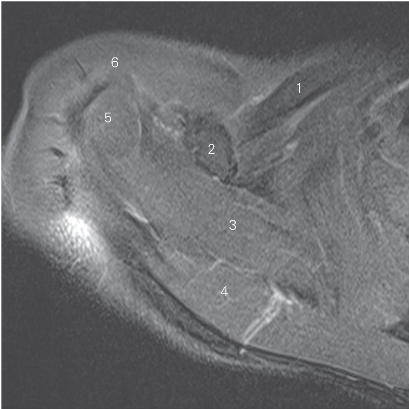

图4-5 经肱骨头上份的横断层MR T2WI FS

1 锁骨 clavicle 2 喙突 coracoid process

3 冈上肌 supraspinatus 4 斜方肌 trapezius

5 肱骨头 head of humerus 6 三角肌 deltoid